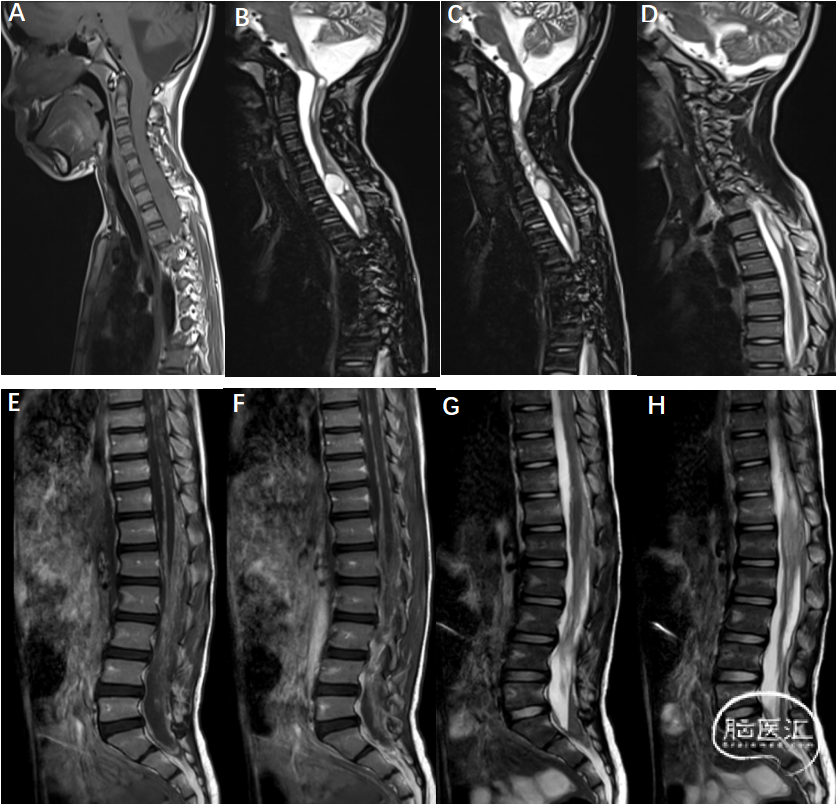

影像资料(全脊柱MRI:2025-11-20)详见下图

A-D:延颈髓交界部明显狭窄,延髓缩小、末端呈鸟嘴状;颈1-胸3水平脊髓粗细不均伴多发囊变,于颈7水平明显囊状扩张,大小约1.7cm×1.2cm×3.3cm,增强其内见结节状强化;椎管内脑脊液信号T1WI与脊髓信号相当,DWI信号高,颈髓受压后移。颅底至胸上段脊膜不规则增厚并强化,局部呈小结节状。影像学诊断:颈胸段脊膜炎、脊髓炎伴硬膜下积脓

E-H:胸12-腰1水平马尾神经冗余,增强后强化不均;椎管内脑脊液信号T1WI与脊髓信号相当,腰髓受压后移,局部包绕马尾终丝。胸段脊膜不规则增厚。影像学诊断:胸12-腰1水平马尾神经冗余,胸腰段脊膜炎伴硬膜下积脓